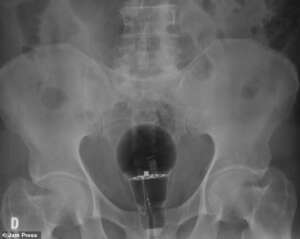

Άναυδοι έμειναν οι γιατροί σε νοσοκομείο της Κολομβίας, όταν διαπίστωσαν πως μια λάμπα βρισκόταν μέσα στον πρωκτό ενός ασθενή, 53 ετών.

Ο ασθενής, ο οποίος δεν έχει κατονομαστεί, πήγε φέτος σε τοπικό νοσοκομείο παραπονούμενος για πόνο στο σημείο. Οι γιατροί δεν είδαν τίποτα κατά τη διάρκεια της φυσικής εξέτασης, αλλά σοκαρίστηκαν όταν μια ακτινογραφία αποκάλυψε μια μεγάλη λάμπα σφηνωμένη, σύμφωνα με τη Daily Mail.

Δεν ήταν σαφές πώς βρέθηκε εκεί ο λαμπτήρας. Δεν ήταν επίσης σαφές πώς αφαιρέθηκε ο λαμπτήρας ή αν το άτομο υπέστη μακροχρόνια βλάβη. Οι γιατροί δήλωσαν ότι ο ασθενής ήταν τυχερός που η λάμπα δεν είχε σπάσει.